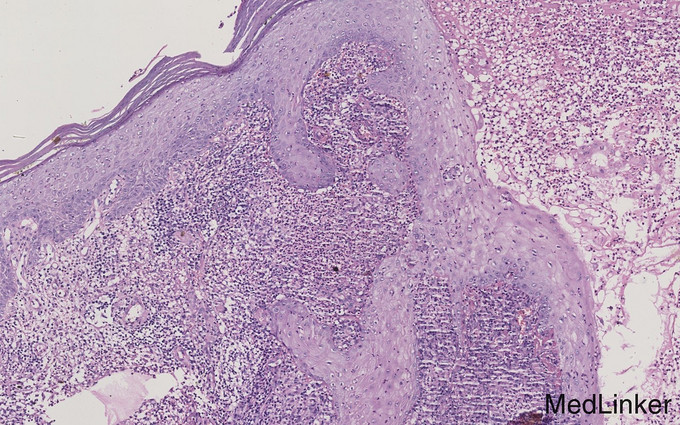

专科检查:左手腕部可见鸡蛋大小溃疡,溃疡周围炎性红斑,红斑上散在蚕豆大小结节。溃疡周边隆起,基底较干燥,无压痛。患者既往体健。否认其他疾病史。 实验室检查:皮肤病理检查:表皮增生,真皮可见弥漫混合炎性细胞性浸润。PAS染色:阴性。真菌镜检:阴性。真菌培养:孢子丝菌。

诊断:孢子丝菌病(固定型)。治疗:伊曲康唑:0.1 p.o bid,酮康唑洗剂、特比萘芬软膏外用1周后复诊。皮疹好转。伊曲康唑胶囊 0.1 p.o bidx30天,10%碘化钾溶液 10ml p.o tidx 30天,黄纱条换药 x 5天,头孢呋辛酯:0.5 p.o tid x 5天。特比萘芬软膏外用。1月后,述面部四肢浮肿,停用碘化钾。继续口服伊曲康唑及抗真菌药外用。1个半月后,皮疹愈合。伊曲康唑继续 0.1 p.o bid x 1个半月。